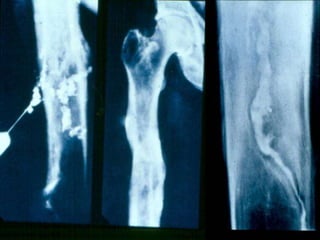

Radiographic Findings

1) X-ray examination

- Usually show bone resorption (patchy loss of density / osteolytic

lesion)

- Thickening & sclerosis around the bone (involucrum)

- Presence of sequestra